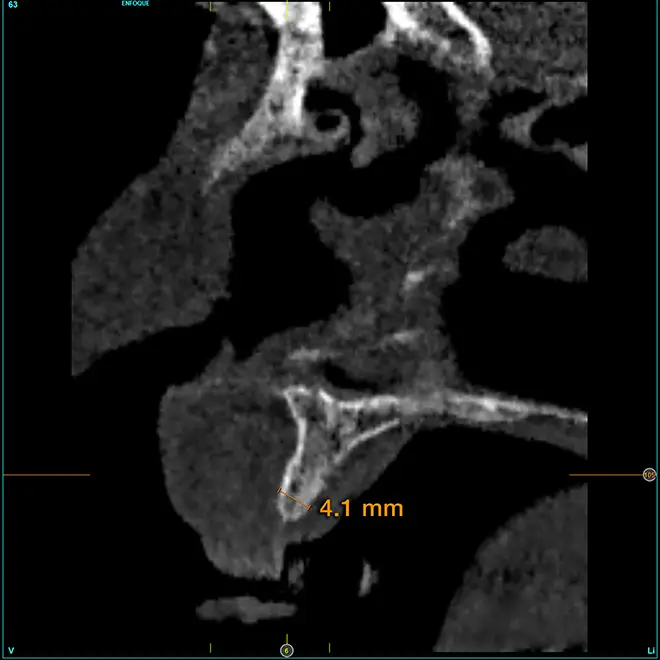

En la zona correspondiente a la pieza 24, tenemos una atrofia extrema también pero en este caso en sentido vertical, con una cresta residual de 3,1 mm de grosor, como podemos ver en el corte seccional del cone-beam (fig. 11). En este caso se planifica la colocación de un implante de 2,5 mm de diámetro y 6,5 mm de longitud (con plataforma reducida de 3 mm -plataforma 3.0, biotechnology institute-) (fig. 12). Igualmente, en la zona anterior de la premaxila, tenemos una situación muy similar donde el volumen óseo es reducido, incluso más que en la zona del segundo cuadrante y, por ello, optamos también por implantes de 2,5 mm de anchura y plataforma de 3 mm (figs. 13-16).

Fig. 11. Corte de planificación de la zona correspondiente a la pieza 24, que presenta una atrofia ósea en anchura extrema con 3,1 mm de anchura residual.